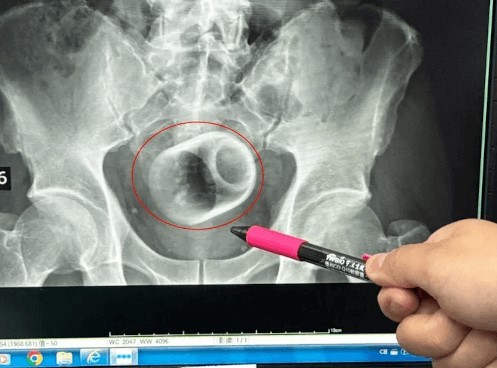

В этот раз видимо во время чаепития.

Чудак заявил доктору, что не знает, как чашка попала в его прямую кишку..

Доктор Ву Кун-Да, хирург из госпиталя в Тайчжуне (Тайвань), рассказал о необычном случае из своей практики.

К нему обратился мужчина, три дня страдавший от вздутия живота и непроходимости кишечника. Что неудивительно, ведь в прямой кишке незнакомца застряла керамическая чашка. При этом удалять посторонний предмет пришлось с помощью открытой операции, разрезав брюшную полость и вскрыв кишечник пациента. Иначе чашку было не подцепить.

Впоследствии смущённый мужчина рассказал доктору, что понятия не имеет, как чашка очутилась внутри его тела. На это Ву Кун-Да лишь заявил, что людям стоит осознавать опасность подобного любопытства и странных опытов над собой. Ну, а если эксперимент очередного чудака пойдёт не по плану, то тут уж надо превозмогать стыдливость и немедленно обращаться за медицинской помощью.

Опять кто-то неудачно поскользнулся..